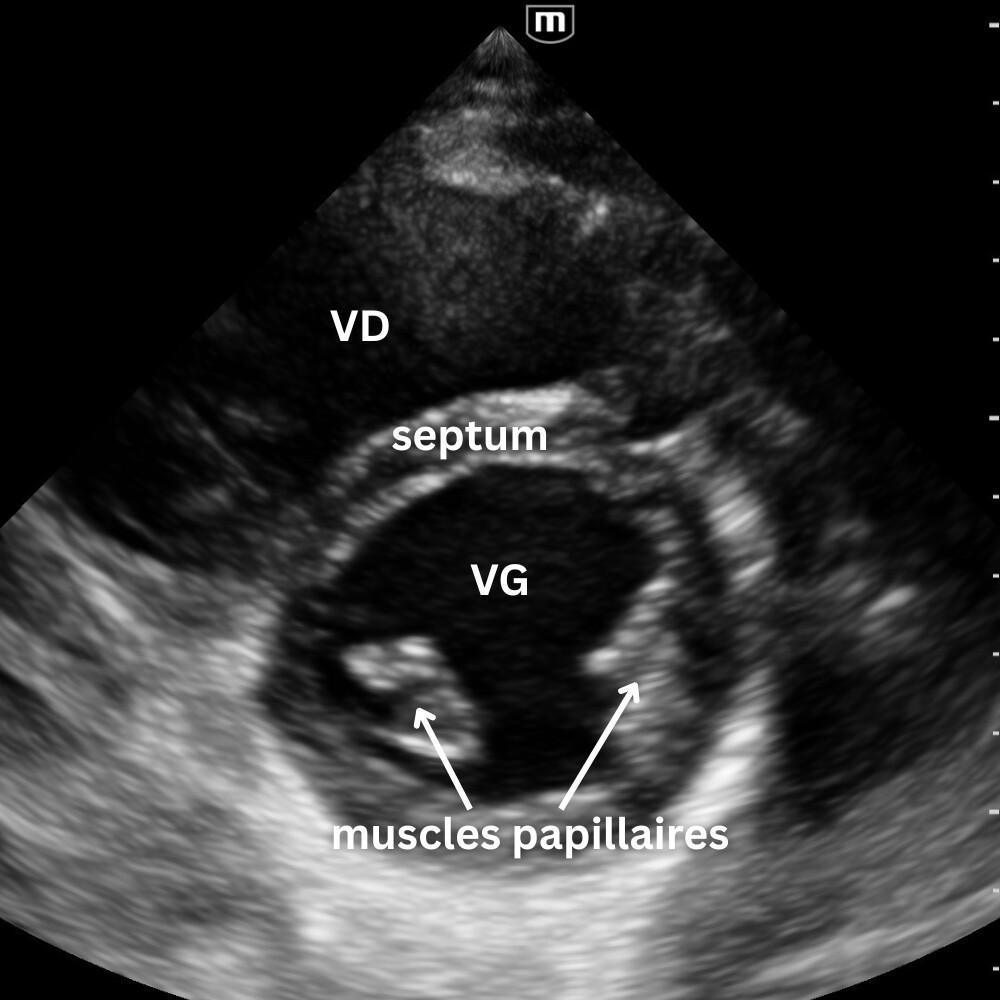

🔹 Vue Parasternale Petit Axe

→ La contraction est-elle harmonieuse ?

Même point d’appui que pour le parasternal grand axe, rotation à 90°, marqueur vers l’épaule gauche.

On observe la coupe circulaire du VG et du VD.

Un VG rond, contractile et homogène = fonction normale.

Un VG aplati ou en “D” = surcharge droite (embolie pulmonaire, HTP, tamponnade).

Une zone hypokinetique/akinetique = ischémie segmentaire.

Vue reine pour la fonction systolique et le septum interventriculaire.

Un léger mouvement de bascule permet d’explorer trois niveaux distincts :

- le plan de la valve mitrale

- le plan des muscles papillaires

- le plan de la valve aortique avec son aspect caractéristique en « signe Mercedes ».